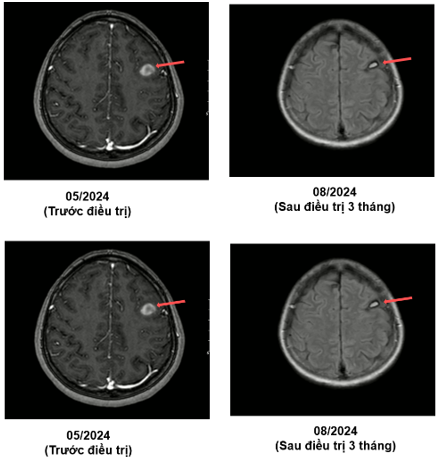

MRI sọ não (05/2024):

Hình 1: Hình ảnh các khối, nốt tổn thương có chảy máu thùy trán phải, góc cầu tiểu não trái, các nốt chảy máu thùy trán trái, thùy thái dương - thùy chẩm phải - theo dõi các tổn thương thứ phát.

MRI sọ não sau điều trị:

Theo dõi định kỳ bằng lâm sàng, chụp CT ngực và MRI sọ não sau 3 tháng, 6 tháng và 15 tháng cho thấy:

- Tổn thương phổi và não giảm kích thước rõ rệt.

- Không xuất hiện tổn thương di căn mới.